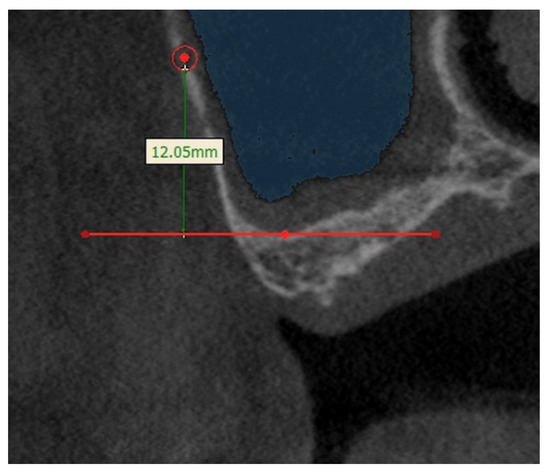

The aim of this study is to evaluate anatomical considerations and assess the volume of the maxillary sinus bone graft. There were sixty-three patients (eighty-three sinuses) who had taken CT scans for implant surgery. Patients included those whose height of the residual alveolar [...] Read more.

The aim of this study is to evaluate anatomical considerations and assess the volume of the maxillary sinus bone graft. There were sixty-three patients (eighty-three sinuses) who had taken CT scans for implant surgery. Patients included those whose height of the residual alveolar bone was less than 5 mm. The position of posterior superior alveolar artery, the thickness of the maxillary sinus wall, and the volume of the maxillary sinus according to the amount of sinus floor elevation were measured. The mean vertical distance of posterior superior alveolar artery was 11.91 ± 4.79 mm from 3.03 mm to 24.05 mm. The mean thickness of the lateral wall was 1.71 ± 0.55 mm in the range of 0.74 mm to 3.93 mm. The volume of 3 mm, 5 mm, 7 mm, and 10 mm from the sinus floor was 0.173 ± 0.11 cm3, 0.526 ± 0.25 cm3, 1.068 ± 0.43 cm3, and 2.184 ± 0.74 cm3 on average, respectively. The knowledge of the posterior superior alveolar artery position, the lateral wall thickness, and the volume of the maxillary sinus can help the clinician for sinus bone graft. Full article